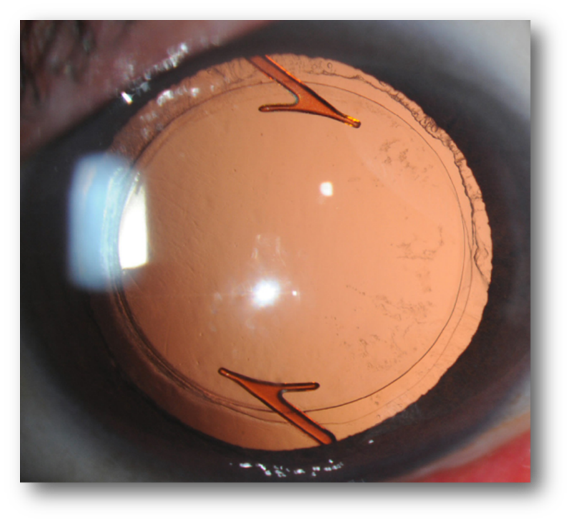

超音波水晶体乳化吸引術では、まず水晶体嚢(水晶体周囲の皮)を残しつつ水晶体前嚢に小さな穴(5~6mmほど)を開け、超音波水晶体乳化器で白濁している白内障部位のみを破砕・吸引します。これにより白内障が除去されます。しかし、このままではレンズが無くなっている状態です。目のピントを合わせるために代わりのレンズが必要になりますので、摘出した水晶体の代わりとして眼内レンズ(人工水晶体)を水晶体嚢の中に挿入します。

眼内レンズはその後、我々眼科医とメーカーの提携開発によって、柔らかいプラスチック型のレンズ(小さな傷から折り曲げるようにして眼内に挿入できる)に改良されました。このレンズは現在のグローバルスタンダードになっています。